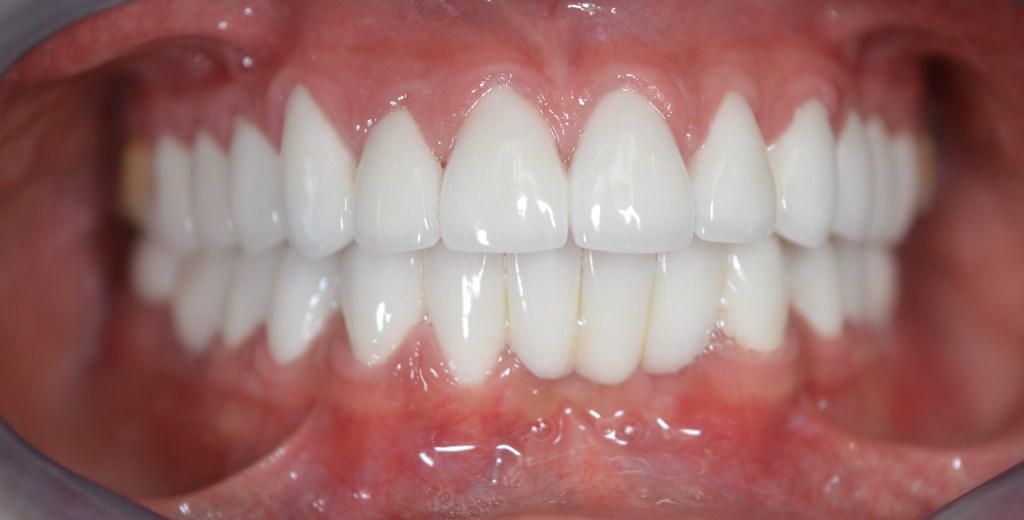

Kozmetikai és funkcionális kezelés: a kopott, elszuvasodott fogak szanálásával, hiányzó frontfogak híddal történő pótlásával, harapás megemelésével.

A választott korona típusa: CAD/CAM (komputer vezérelt tervezés/megmunkálás) technológiával készült cirkónium (fémmentes) szóló koronák, front híd.

A választott fogszín: BL 3 .

A protetikai munka elkészülésének ideje: 10 munkanap.